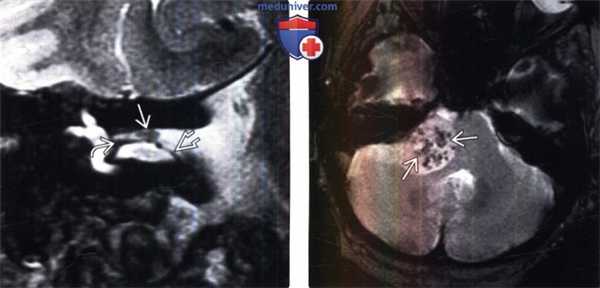

(Слева) МРТ, постконтрастное Т1 -ВИ, режим подавления сигнала от жира, аксиальный срез: у пациента с левосторонней ней-росенсорной тугоухостью определяется небольшая контрастируе-мая вестибулярная шваннома, располагающаяся во внутреннем слуховом проходе, а также 3-мм фундальный колпак из СМЖ, расположенный латерально по отношению к опухоли.

(Справа) МРТ, последовательность CISS, аксиальный срез: у того же пациента в области ВСП на фоне гиперинтенсивной СМЖ определяется «дефект наполнения». Вестибулярная шваннома легко диагностируется с применением последовательности CISS. Заполненный СМЖ фундальный колпак лучше визуализируется на Т2-ВИ или CISS.

(Слева) Высокоразрешающая тонкосрезовая МРТ, Т2-ВИ, корональный срез: определяется 2-мм вестибулярная шваннома. Образование визуализируется выше серповидного гребня. Кроме того, в латеральной части ВСП наблюдается петля передней нижней мозжечковой артерии.

(Справа) МРТ, Т2* GRE, аксиальный срез: в расположенном в области ММУ компоненте крупной вестибулярной шванномы определяются петехиальные микрокровоизлияния. Такой признак очень характерен для вестибулярной шванномы.